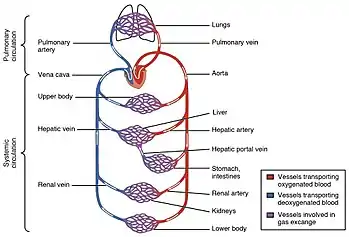

A capillary is a small blood vessel, from 5 to 10 micrometres in diameter, and is part of the microcirculation system. Capillaries are microvessels and the smallest blood vessels in the body. They are composed of only the tunica intima (the innermost layer of an artery or vein), consisting of a thin wall of simple squamous endothelial cells.[2] They are the site of the exchange of many substances from the surrounding interstitial fluid, and they convey blood from the smallest branches of the arteries (arterioles) to those of the veins (venules). Other substances which cross capillaries include water, oxygen, carbon dioxide, urea,[3] glucose, uric acid, lactic acid and creatinine. Lymph capillaries connect with larger lymph vessels to drain lymphatic fluid collected in microcirculation.

Blood flows from the heart through arteries, which branch and narrow into arterioles, and then branch further into capillaries where nutrients and wastes are exchanged. The capillaries then join and widen to become venules, which in turn widen and converge to become veins, which then return blood back to the heart through the venae cavae. In the mesentery, metarterioles form an additional stage between arterioles and capillaries.

Individual capillaries are part of the capillary bed, an interweaving network of capillaries supplying tissues and organs. The more metabolically active a tissue is, the more capillaries are required to supply nutrients and carry away products of metabolism. There are two types of capillaries: true capillaries, which branch from arterioles and provide exchange between tissue and the capillary blood, and sinusoids, a type of open-pore capillary found in the liver, bone marrow, anterior pituitary gland, and brain circumventricular organs. Capillaries and sinusoids are short vessels that directly connect the arterioles and venules at opposite ends of the beds. Metarterioles are found primarily in the mesenteric microcirculation.[5]